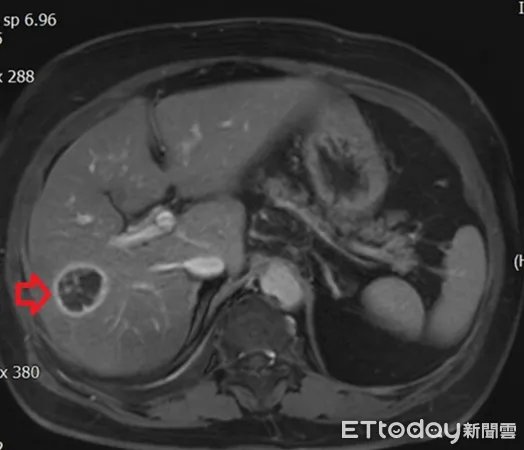

▲年近8旬患者患有多重慢性病,檢查又發現肝癌。(圖/醫師提供,下同)

年近8旬的許奶奶患有慢性肺病、心臟衰竭、糖尿病、高血壓等多種慢性疾病,半年前回診發現肝指數過高,感染科醫師遂安排腹部超音波檢查,結果發現脂肪肝及肝臟一顆約3公分大腫瘤。醫師指出,考量患者肝功能及身體狀況,手術風險高,醫療團隊以腫瘤射頻燒灼術治療,許奶奶也在術後3天平安出院。

肝癌的診斷除了觀察臨床表現外,還需藉由抽血檢查檢驗肝功能狀態,並利用腹部超音波、電腦斷層或核磁造影等相關檢查確認腫瘤型態、大小以及是否有轉移。在手術治療方面,除了傳統開腹手術、微創腹腔鏡或達文西手術外,尚有腫瘤射頻燒灼術的選擇,主要運用於腫瘤小於2至3公分的患者或心肺功能無法負荷麻醉或手術風險較高的病患。